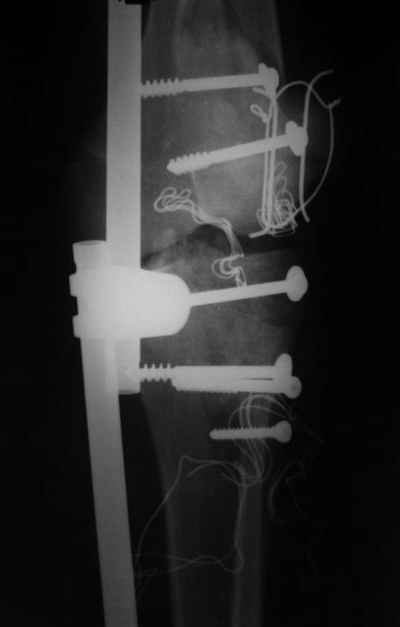

Re: открытый перелом мыщелков бедра, латерального

Вид раны на сегодня...

4 cутки после травмы.